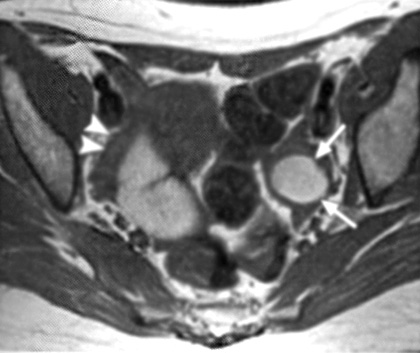

Εικόνα 3. Πυελική ενδομητρίωση με σοβαρές συμφύσεις. Οβελιαία τομή με καταστολή του λίπους στην Τ1 ακολουθία (Α) και κλασική Τ2 οβελιαία τομή (Β), όπου απεικονίζονται πολλαπλές ενδομητριωσικές κύστεις στον δουγλάσειο. Μικρά ενδομητριώματα με υψηλής έντασης σήμα αναγνωρίζονται στην Τ1 ακολουθία με καταστολή του λίπους (βέλη στη τομή Α). Οπίσθια κλίση της μήτρας με ανύψωση του οπισθίου κολπικού θόλου (κεφαλή βέλους στη τομή Β), ενδεικτικά παρουσίας σοβαρών συμφύσεων στον δουγλάσειο. Επιπλέον διαπιστώνεται αδενομύωση στον ορογόνο της οπισθίας επιφάνειας του μυομητρίου (βέλη στην τομή Β).

Επιπλέον, στη μαγνητική τομογραφία οι συμφύσεις εμφανίζονται ως χαμηλής έντασης σήματος νηματοειδείς σχηματισμοί, οι οποίοι καθιστούν ασαφείς τις διαχωριστικές επιφάνειες δύο παρακείμενων οργάνων και μπορούν ενίοτε να προσλαμβάνουν σκιαστικό, χωρίς ωστόσο να αυξάνουν την ευαισθησία ή την ειδικότητα της μαγνητικής τομογραφίας. Σύμφωνα με μελέτη των Katayama και συν. εκτιμήθηκε η αξία της μαγνητικής τομογραφίας στην εκτίμηση των πυελικών συμφύσεων χρησιμοποιώντας μια ειδική τεχνική και διαπιστώθηκε πως η ευαισθησία και η ειδικότητα της μεθόδου είναι 72.5% και 87.4% αντίστοιχα. Η οπίσθια κλίση και καθήλωση της μήτρας στον δουγλάσειο, η προσκόλληση των ωοθηκών μεταξύ τους και στην οπίσθια επιφάνεια της μήτρας, η γωνίωση των εντερικών ελίκων, η ανύψωση των οπίσθιων κολπικών θόλων, η εγκυστωμένη συλλογή υγρού και η παρουσία υδροσαλπίγγων αποτελούν έμμεσα ευρήματα, ενδεικτικά συμφύσεων (εικόνα 3).(15,16)